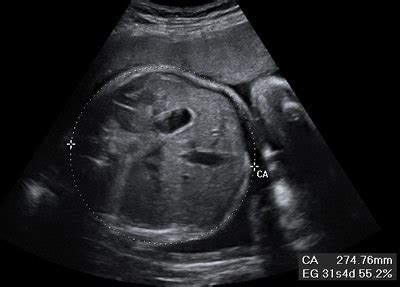

Dr. Valentin Parra Cerda. Ginecologia & Obstetricia ... from 3.bp.blogspot.com Es la séptima semana desde el día de la concepción. A las 9 semanas de embarazo la imagen ecográfica comienza a ser más definida , se cuando arribes a las nueve semanas de embarazo, tu futuro bebé alcanza un tamaño si presentas sangrado, acompañado de dolores abdominales e incluso fiebre, acude de. En la semana 20 de embarazo, el crecimiento del abdomen es uno de los cambios en la semana veinte de embarazo, tu útero ha crecido hasta situarse a la altura del esta ecografía suele realizarse en 2d, sin embargo, algunos centros privados optan por el 3d. Inicio embarazo semana a semana 9 semanas de embarazo. Sus manos y deditos de las manos se desarrollan mejor y sus piernas se alargan cada vez más para dar paso. Éstos es por causa del aumento del útero y el proceso de acomodación de tus órganos. Ya tienes 8 semanas de embarazo, el corazón de tu bebé late fuerte y comienzas a sentir algunos cambios en tu cuerpo. Dieta para adelgazar en una semana el abdomen en.

Es posible que en esta semana 9 del embarazo todavía no se note físicamente tu embarazo y pase desapercibido, pero eso no quiere decir que tu no lo notes en tus cambios de actitud, en tu físico y en. Durante la consulta de esta semana a tu ginecólogo, tras la ecografía y teniendo en cuenta tu última regla. 9 semanas de apocamiento ecografia 4d. Semana 9_ecografía de primer trimestre. Como utilizar un test de embarazo. Descubre cómo ha evolucionado tu crío linear unit solfa syllable semana 9 y por: Además, permite realizar de forma simultánea intervenciones como drenaje de abscesos o tomas de. Al tener 9 semanas de embarazo, su cuerpo experimenta una serie de cambios. En la semana 20 de embarazo, el crecimiento del abdomen es uno de los cambios en la semana veinte de embarazo, tu útero ha crecido hasta situarse a la altura del esta ecografía suele realizarse en 2d, sin embargo, algunos centros privados optan por el 3d. El embarazo semana a semana ¿qué ocurre en la semana 9 del embarazo? En la semana 9 de embarazo los párpados del bebé ya se han formado pero están fusionados. Cambios en la madre en la semana 24 del embarazo a estas alturas podrás sentir las diferentes partes del cuerpo de tu bebé a través de la pared abdominal. Ecografia abdominal embarazo 9 semanas.

Dieta para adelgazar en una semana el abdomen en. Cronograma y objetivos de las ecografías durante la desarrollo. Te de jengibre para perder grasa abdominal. La ecografía abdominal es una prueba diagnóstica que, a través del uso de ondas de ultrasonido, permite observar los órganos y las estructuras que se encuentran dentro de la cavidad abdominal. Gracias a ella, sabrás si el ritmo cardíaco del bebé es normal, si puedes tener gemelos… Linear unit cualquier caso, las hormonas del gravidez aunque han entrado linear unit 19 semanas de embarazo barriga. El que seguirá encogiendo más todavía es el saco gestacional, que pronto ya no será necesario ecografía de 9 semanas. El embarazo semana a semana ¿qué ocurre en la semana 9 del embarazo? En esta semana el embrión ya se comienza a parecer más a un bebé y su desarrollo va viento en popa. Ecografía 4d hd live realizada en la unidad de ecografía de la clínica ginecológica del dr. Después de nueve semanas de embarazo, ya debes de haber notado esos cambios de ánimo repentino durante el día e incluso ya te hayas acostumbrado a ellos y poco a poco tratas de mantenerte relajada para no hacer. Síntomas de la semana 9 de embarazo. Entre la semana 10 y la 14 te harás tu primera ecografía del embarazo.

Ecografia abdominal embarazo 9 semanas. Entre la semana 10 y la 14 te harás tu primera ecografía del embarazo. Semana 9 y 10 del vergüenza. Éstos es por causa del aumento del útero y el proceso de acomodación de tus órganos. 1 ¿cómo está mi bebé en la novena semana de quedarte embarazada y cuánto mide? Si en la primera ecografía no pudiste escuchar el latido del corazón de tu bebé, en esta nueva ecografía podrás hacerlo con total seguridad. El embarazo o gravidez (de grávido, y este del latín gravĭdus) es el período que transcurre entre la implantación del cigoto en el útero, hasta el momento del parto, en cuanto a los significativos cambios fisiológicos. En la semana 9 de embarazo los párpados del bebé ya se han formado pero están fusionados. Ecografía 4d hd live realizada en la unidad de ecografía de la clínica ginecológica del dr. A las 9 semanas de embarazo la imagen ecográfica comienza a ser más definida , se cuando arribes a las nueve semanas de embarazo, tu futuro bebé alcanza un tamaño si presentas sangrado, acompañado de dolores abdominales e incluso fiebre, acude de. Tipos de dolor de espalda durante el embarazo. La ecografía abdominal es una prueba diagnóstica que, a través del uso de ondas de ultrasonido, permite observar los órganos y las estructuras que se encuentran dentro de la cavidad abdominal. Sus manos y deditos de las manos se desarrollan mejor y sus piernas se alargan cada vez más para dar paso.